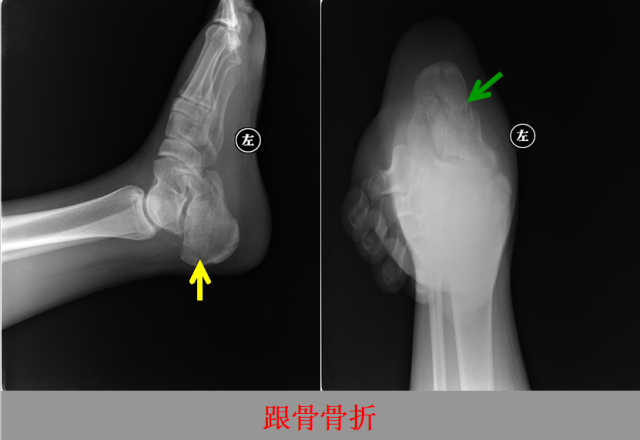

骨折篇

定义:骨折{Fracture}是指骨的完整性和连续性的折裂或粉碎。包括创伤性骨折、疲劳性骨折和病例理性骨折。 临床上以创伤性骨折*常见。